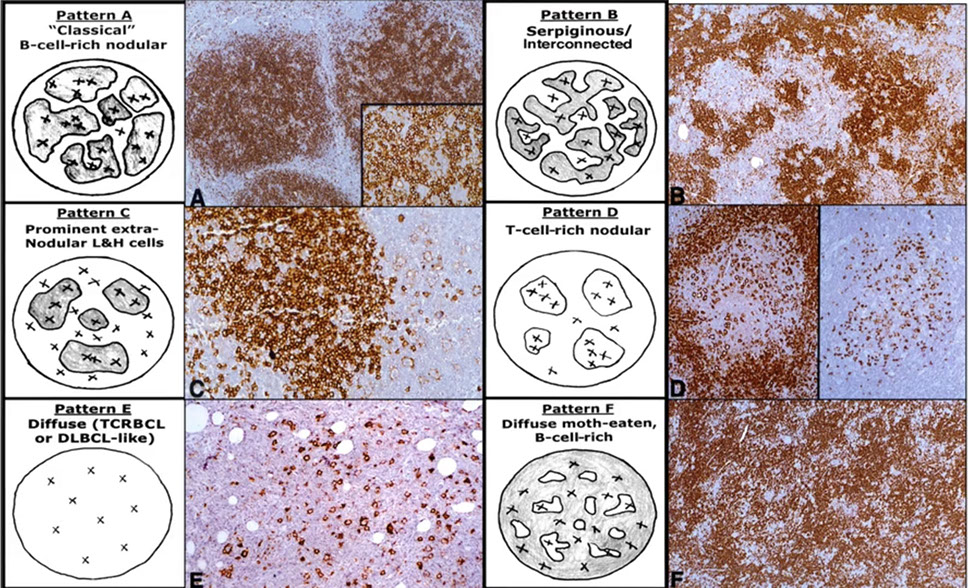

Nodular lymphocyte predominant Hodgkin lymphoma (NLPHL)